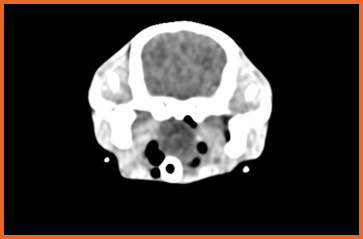

我們提供留院服務並擁有相應的治療設施,亦是小數備有CT電腦掃描及MRI磁力共振等大型醫療儀器的診所及醫院。